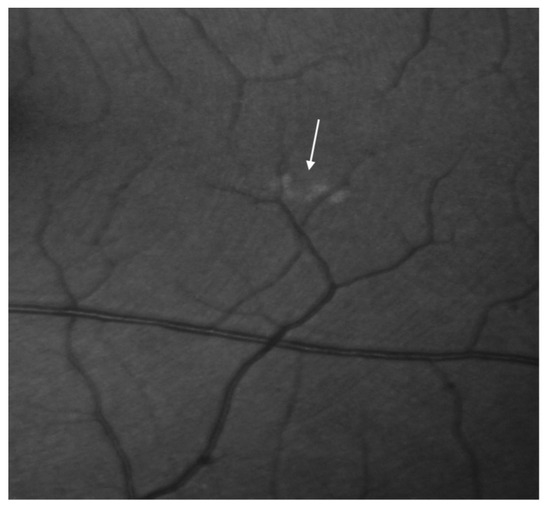

The retinal drusen were observed in the retina of the left eye (Figure 5).

Figure 5.

Focal drusen around the subretinal region of the left eye demonstrated in the fluorescein angiography (the arrow demonstrates focal drusen).